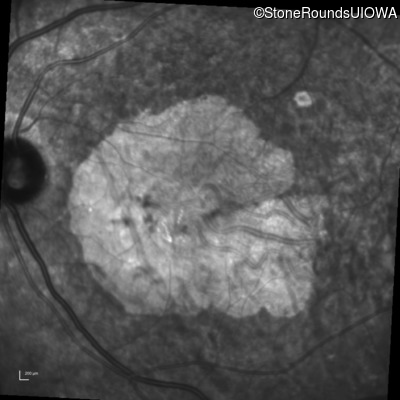

AR Stargardt Disease (IIA)

AR Stargardt Disease

ABCA4

Gly607Arg GGG>AGG

IVS30+1321 A>G

AR

Disease:

Gene:

Allele 1:

Allele 2:

Inheritance: